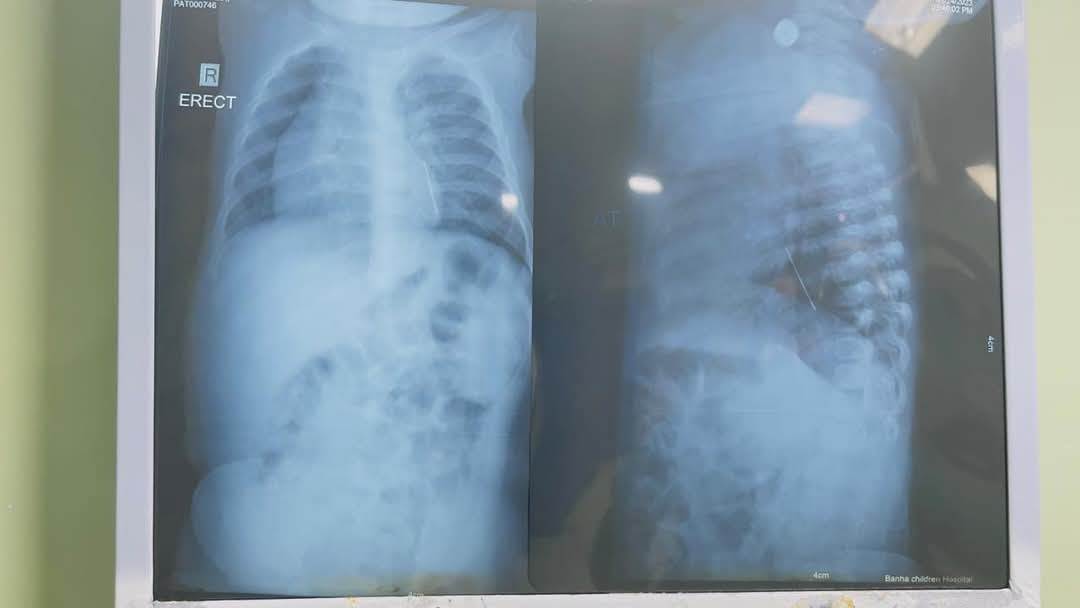

وقال بيان للمستشفى، إن الصغيرة حضرت وكانت تعاني من آلام بالصدر، وتم حجزها بالمستشفى وإجراء الإشاعات والفحوصات الطبية اللازمة، وتبين وجود دبوس طرحة على الصدر.

أجريت العملية، برئاسة الدكتور محمد محمد متولي، استشاري جراحة الأطفال، والدكتور عمرو عبدالملك، أخصائي الجراحة، وفريق التخدير، من استخراج الدبوس.